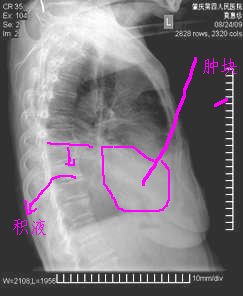

以下是引用zxl51642在2009-9-8 11:39:00的发言:[br]右侧胸腔积液,叶间裂积液,不排除右下占位并阻塞性不张;头晕头痛4年恶心、呕吐2h入院,建议颅脑ct平扫。